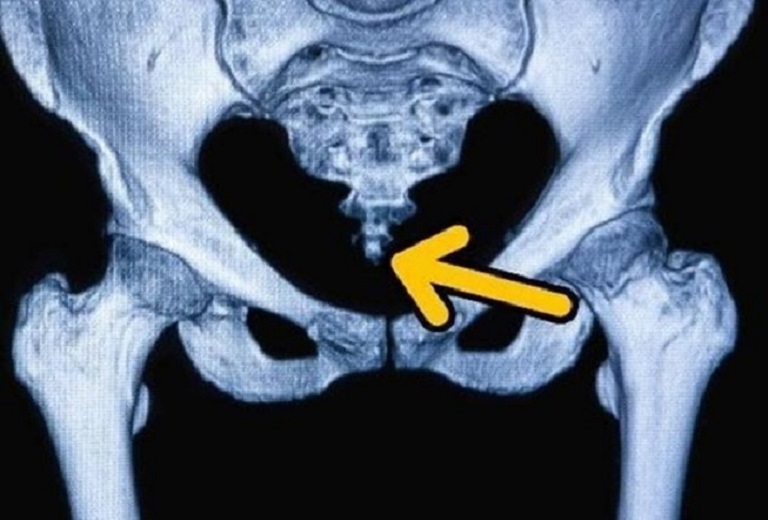

Đau xương cụt (Coccydynia hoặc Tailbone Pain) xảy ra do xương cụt bị mất ổn định dẫn đến viêm các khớp lân cận (đặc biệt là khớp cùng chậu). Cơn đau ở xương cụt sẽ chuyển biến từ nhẹ đến dữ dội và thường tăng nặng khi ngồi xuống, đứng lên hoặc ngả người ra sau khi ngồi trên ghế.

2. Nguyên nhân dẫn đến đau xương cụt

Cơn đau xương cụt có thể xuất hiện từ chính những tổn thương tại xương cụt, nhưng cũng có thể là hậu quả của một vấn đề sinh lý hoặc bệnh lý nào khác bên trong cơ thể, cụ thể:

Xương cụt bị dị dạng hoặc lệch vị trí bẩm sinh.

Chấn thương khiến xương cụt bị rạn nứt, gãy hoặc lệch khỏi vị trí.